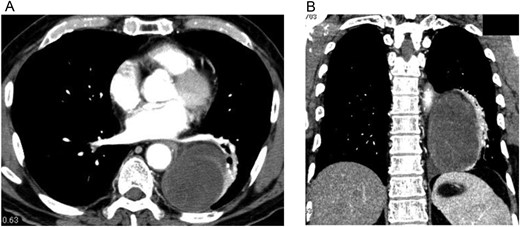

A 74-year-old man was referred to our hospital after a left middle and posterior mediastinal tumor was detected on computed tomography (CT) performed as an examination for dry cough in other hospital. CT about 2 years earlier had shown a 3.2 × 2.4-cm lipomatous tumor at the left hilum adjacent to the left lower pulmonary vein (Fig. 1), and that lipomatous tumor was considered the origin of the present mediastinal tumor. Contrast-enhanced CT performed in our hospital showed a heterogeneous tumor, displacing the left lower lobe of the lung, and measuring 10 × 7.4 × 6 cm on horizontal and coronal sections (Fig. 2A and B). Magnetic resonance imaging showed a hyperintense marginal region with central hypointensity on T1-weighted imaging, and heterogeneously high intensity in the whole tumor on T2-weighted imaging. We scheduled surgical resection, and the patient was admitted to our hospital 3 weeks after the first visit. Chest radiography showed rapid growth of the left intrathoracic tumor (Fig. 3A and B), and CT revealed a tumor measuring 11.4 × 8 × 6.2 cm without pleural effusion or hemothorax.

CT from another hospital 2 years earlier shows a 3.2 × 2.4-cm lipomatous tumor at the left hilum adjacent to the left lower pulmonary vein.